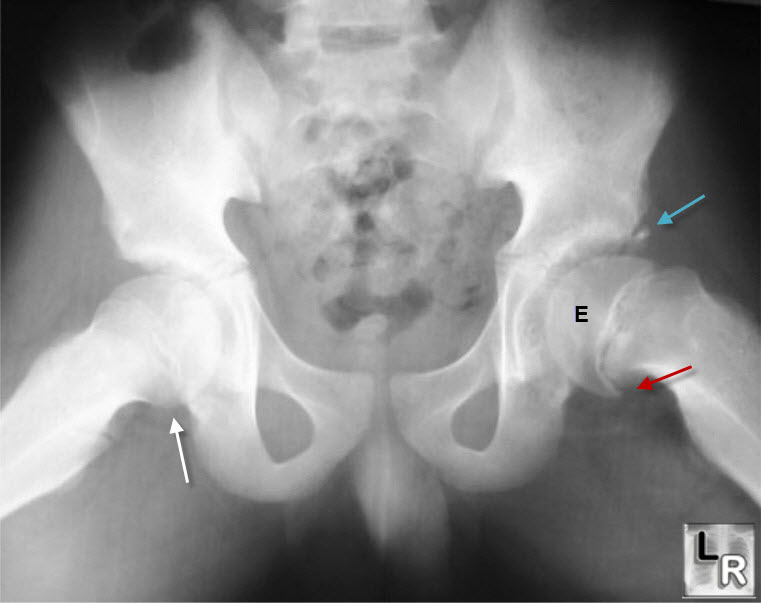

Slipped Upper Femoral Epiphysis – Radiology Cases

radiologycases.my

radiologycases.my

epiphysis femoral upper slipped pelvis radiology surgical radiograph intervention radiologycases

Slipped Upper Femoral Epiphysis – Radiology Cases

radiologycases.my

radiologycases.my

femoral epiphysis upper slipped radiology radiologycases pelvis